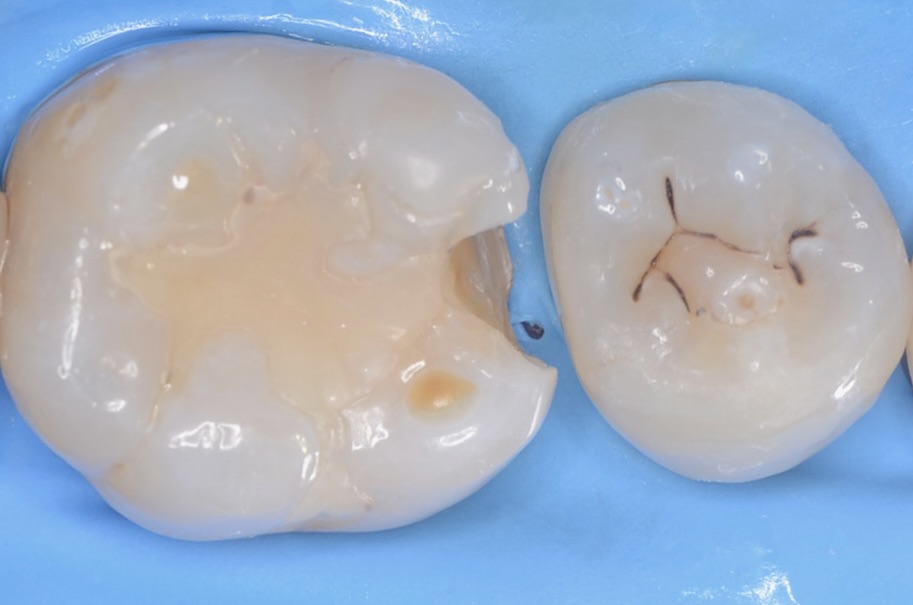

5番遠心

虫歯を取り除いたところです。 -

拡大

5番の辺縁隆線を削らないよう、最小限の切削量で治療します。 -